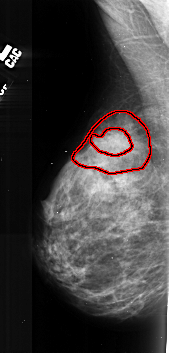

ics_version 1.0 filename A-1027-1 DATE_OF_STUDY 25 1 1993 PATIENT_AGE 48 FILM FILM_TYPE REGULAR DENSITY 4 DATE_DIGITIZED 7 1 1998 DIGITIZER DBA 21 SEQUENCE LEFT_CC LINES 4801 PIXELS_PER_LINE 2746 BITS_PER_PIXEL 16 RESOLUTION 42 OVERLAY LEFT_MLO LINES 5281 PIXELS_PER_LINE 2521 BITS_PER_PIXEL 16 RESOLUTION 42 OVERLAY RIGHT_CC LINES 4576 PIXELS_PER_LINE 2326 BITS_PER_PIXEL 16 RESOLUTION 42 NON_OVERLAY RIGHT_MLO LINES 5476 PIXELS_PER_LINE 2506 BITS_PER_PIXEL 16 RESOLUTION 42 NON_OVERLAY |

FILE: A_1027_1.LEFT_MLO.OVERLAY TOTAL_ABNORMALITIES 1 ABNORMALITY 1 LESION_TYPE MASS SHAPE LOBULATED MARGINS SPICULATED ASSESSMENT 5 SUBTLETY 4 PATHOLOGY MALIGNANT TOTAL_OUTLINES 2 BOUNDARY CORE |